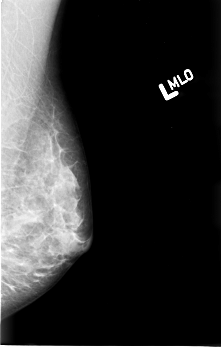

B_3008_1.LEFT_MLO

LEFT_MLO LINES 4520 PIXELS_PER_LINE 2872 BITS_PER_PIXEL 12 RESOLUTION 50 NON_OVERLAY